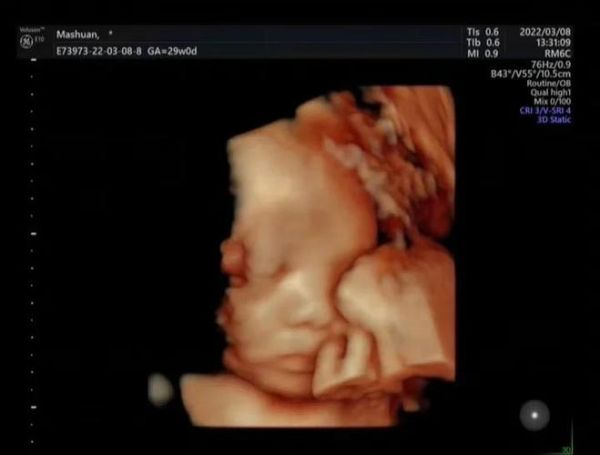

二、四维彩超到底“超”些什么?

1. 头部与颜面系统

系统B超是二维切面+彩色多普勒,侧重测量与诊断;四维在二维基础上实时三维成像,可立体观察颜面、手足姿势。两者互补,缺一不可。